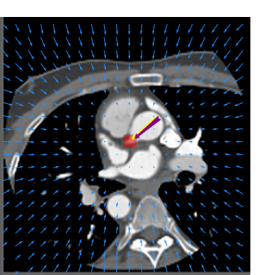

Finally, the proposed network was evaluated for the detection of five additional landmarks: the left coronary ostium, the bifurcation of the LM into the LAD and the LCx, and the origin of the left, non-coronary, and right aortic valve commissures (see Fig. 2). Fig 3 shows vector fields visualizing the predicted displacement vectors in three viewing planes in an image from the test set (for more results, see Appendix). Table 3 lists the Euclidean distance errors between the predicted landmark locations and the reference landmark locations. In addition, box-and-whiskers plots are shown in Fig 4. The best results were obtained for the origin of the right aortic valve commissure. Detection of the origin of the left aortic valve had the most narrow distribution. Outliers were seen during detection of the right ostium, the bifurcation of the LM, and the origin of the non-coronary, and the left aortic valve commissure.

Figure 3: Vector fields visualizing the predicted displacement vectors in the axial, coronal, and sagittal plane in an image from the test set where detection of the right coronary ostium was performed. The magnitudes of the vectors should point at the right ostium, but they are rescaled for visualization purposes. The red squares indicate posterior probabilities larger than 0.5, obtained by the classification network for image patches. Reference and computed landmark annotations are indicated with a yellow and purple arrow, respectively.